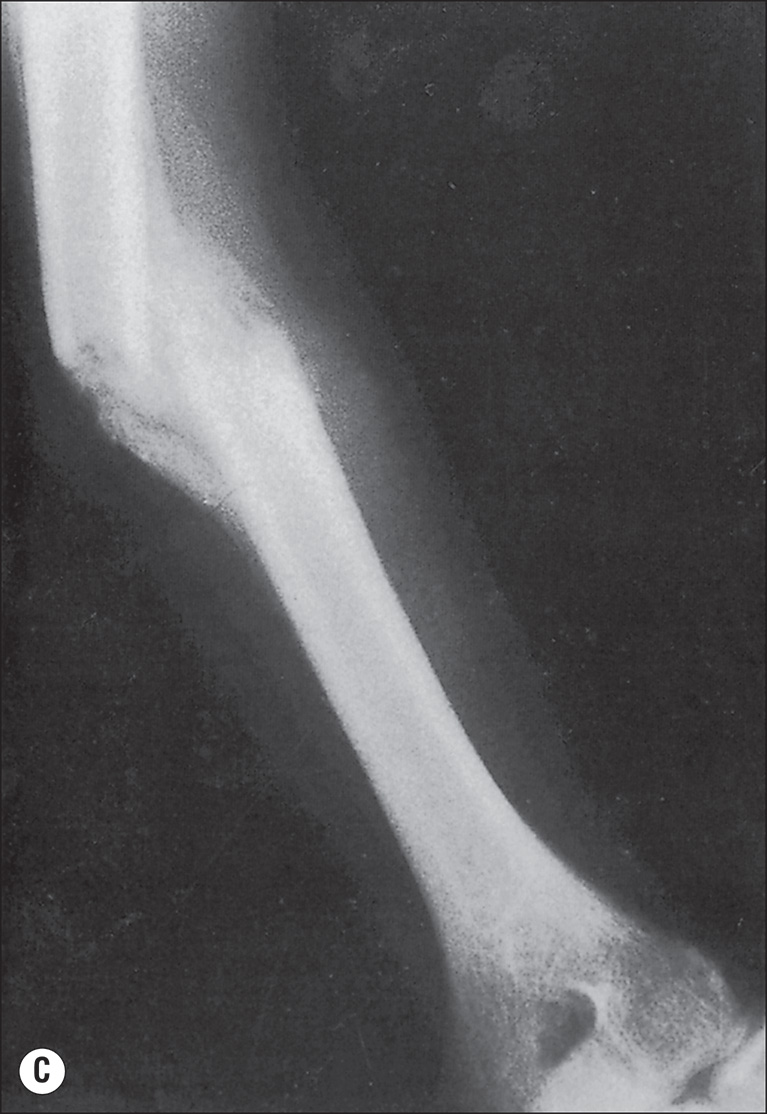

Although fractures complicate burn treatment and occasionally delay mobilization of patients, their management need not be complex. Fractures in extremities not burned can be treated by manipulative reduction and cast immobilization, by open reduction and fixation, with an external fixator, or with skeletal traction ( Fig. 41.4 ). Fractures in extremities with first-degree or superficial second-degree burns can be managed in the same way. Deep second- and third-degree burns present a different problem only with respect to the early bacterial colonization of third-degree burns and the degradation of deep second-degree burns to full-thickness burns that will in turn become colonized. There is a precious window of time when fractures requiring open reduction and internal fixation (ORIF) can be definitively treated without increased risk for infecting the bone; however, fracture reduction and stabilization are so important in the functional management of a severely burned patient that the risk for bone infection should be acknowledged and shouldered at any postburn stage. English and Carmichael showed that if fractures were treated with open reductions within the first 48 hours postburn, the risk of infection is minimal. Therefore early stabilization is encouraged in the first 48 hours before the risk of infection increases. Newer studies, however, suggest that the higher rate of infection and complications correlates more with severity of the injury than the method and time of fixation. Largely, there is still no consensus on treatment choice and timing. ,

(A) This 15-year-old boy sustained closed fractures of the right femur, left tibia, and left humerus at the time of a 46% total body surface area burn involving mainly the trunk and right lower extremity. The femur and humerus fractures were treated in skeletal traction. Suspension of the right lower extremity aided management of circumferential deep burns of that extremity. Lesser burns of the left leg made it possible to treat the minimally displaced fracture of the left tibia in a circular cast. All fractures consolidated in 6 weeks in satisfactory alignment. (B) Fracture of the left humerus as it appeared at the time of admission to the hospital. (C) At 5 weeks after injury, the fracture shows a maturing callus. Traction was discontinued at 6 weeks.